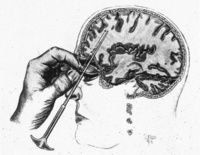

前腦葉白質切除術當實行這一手術時,醫生需要在病人的顱骨兩側各鑽一個小孔,然後將腦白質切斷器從洞中伸入病患腦部,在每側選擇三個位置實施手術。這個儀器的外形就像是一把修長而精緻的螺絲刀,不過它的頭部側面開了口而且沒有尖端。然後醫生需要拉動手柄,開口處的鋼絲在拉動作用下便會凸起,切斷神經纖維。

經眶前額葉白質切斷術示意圖正在手術中的弗里曼同莫尼斯一樣,美國醫生沃爾特·弗里曼也參加了1935年的倫敦會議。

起初,他使用的是同莫尼斯一樣的手術方式,很快他就發展出自己的一種更加迅速便利的手術方式。在他的手術中,需要的工具是一個類似於冰錐的錐子和一個榔頭,病人被施以電擊以代替藥物麻醉。手術時將錐子經由眼球上部從眼眶中鑿入腦內,破壞掉相應的神經。這一過程十分迅速,而且某些情況甚至不需要手術室就可以施行。